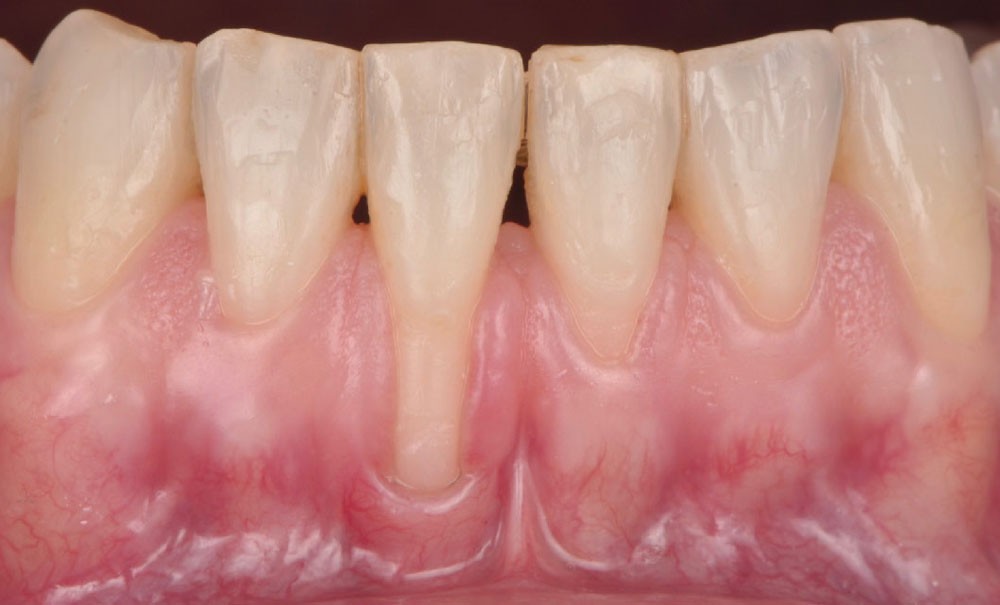

L’examen clinique révèle la présence de récessions gingivales vestibulaires affectant les dents 3.1 et 4.1 (fig. 1a). Selon la classification de Cairo, il s’agit de récessions de type RT2, caractérisées par une perte d’attache interproximale inférieure à la perte d’attache vestibulaire [1]. La ligne amélo-cémentaire (LAC) est identifiable (A) sans perte de substance dentaire (-) [2].

L’analyse du phénotype parodontal met en évidence une gencive fine et transparente (phénotype fin), associée à une bande kératinisée réduite, voire absente. Le sondage parodontal confirme la stabilité du parodonte. La récession la plus profonde, observée sur la dent 4.1, mesure 6 mm (fig. 1b).